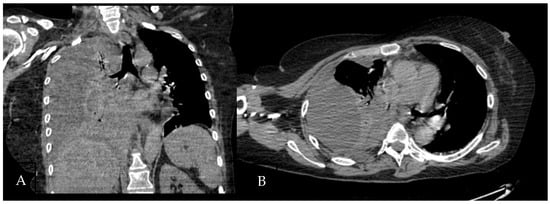

Figure 5. Chest CT scan of the mediastinal window in the coronal (A) and axial (B) plane, showing fluid collection in the medium–lower parts of the right hemithorax (maximum axial dimeters of 19 × 13 cm; craniocaudal extension of 16 cm) with thickened walls and contrast enhancement. There is also a complete atelectasis of middle and lower lobes and partial atelectasis of the upper lobe.

A 60-year-old Caucasian man was admitted to our hospital with a history of worsening pain at the base of the right hemithorax and feeling generally unwell for over one month. The patient’s past medical history included coronary heart disease, with a percutaneous coronary intervention in 2014. He smoked a half-pack of cigarettes per day for 40 years and had no history of respiratory disease. The CT chest scan showed a fluid collection in the medium–lower parts of the right hemithorax with thickened walls and contrast enhancement (Figure 5). This collection appeared in continuity with further smaller fluid collections with thickened walls, contrast enhancement, and confluence and caused the complete atelectasis of the middle and lower lobes and the partial atelectasis of the upper lobe, as well as middle and inferior lobar bronchus occlusion.